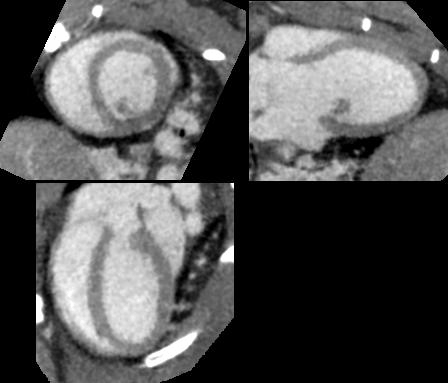

Cardiac gating with 20 phases per R-R interval

• Courtesy of: D. Panetta and P.A. Salvadori, IFC-CNR Pisa